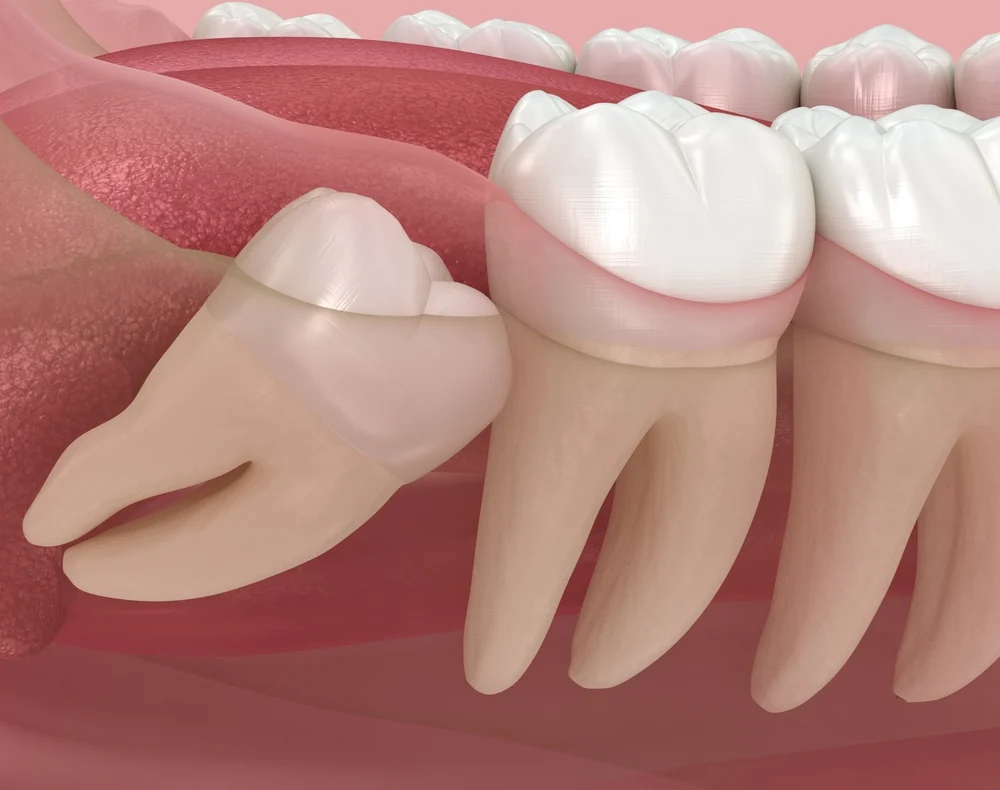

Wisdom Tooth Removal in Singapore: Surgical Extraction Explained

Wisdom tooth removal is a common dental procedure in Singapore, especially among young adults and working professionals. While some wisdom teeth can be removed through simple extraction, many cases require a more complex approach known as surgical extraction. This method is typically necessary when the wisdom tooth is impacted, partially erupted, or positioned in a […]

Wisdom Tooth Removal in Singapore: Simple Extraction Explained

Wisdom tooth removal is one of the most commonly performed dental procedures in Singapore. While many people associate wisdom tooth removal with surgery, not all wisdom teeth require surgical extraction. In fact, for certain cases, wisdom teeth can be removed through a straightforward and minimally invasive procedure known as simple extraction. Understanding the difference between […]